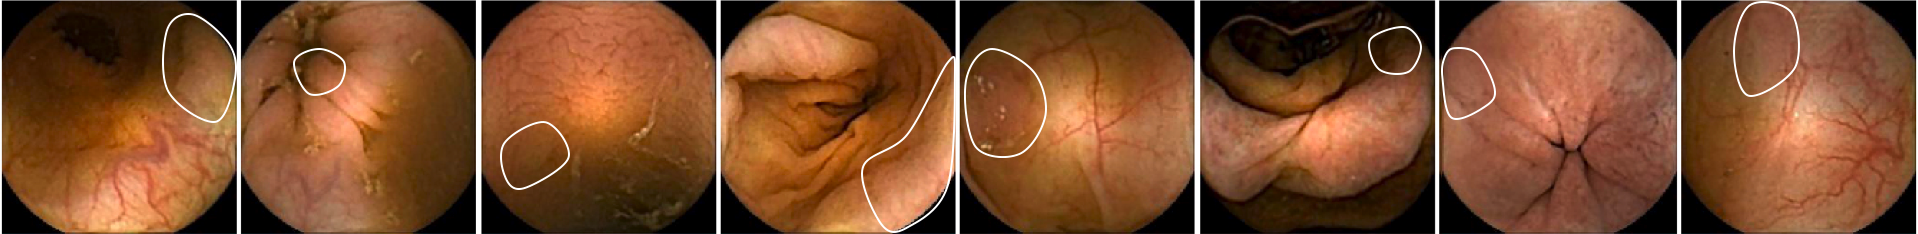

Figure 6 shows 9 polyp samples of different sizes and morphologies.

Figure 11 shows eight polyp images where the system has not obtained enough features to predict the frame as polyp. Each image shows a boundary with the location of the polyps. These difficult cases are complex to detect in single images by the system. The evaluation of a whole sequence of images where the polyp is seen facilitates detection by the human eye. Due to the complexity of polyp detection, sometimes is easier for humans to detect them through the sequence.